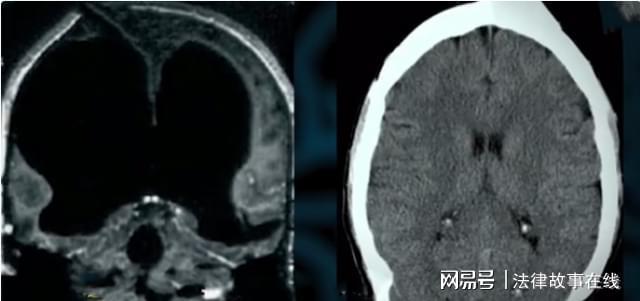

马克为了早点治好病,于是来到了医院做检查,检查结果出来的那一瞬间,让医生有些头发发麻。随后医生让马克呆在原地不要动,他则是前去请了谢菲尔德医院的脑神经科教授约翰·罗博,大约过了不到10分钟的时间。这位教授了解完情况后立即来到了办公室,约翰博士经过细致地查看,果然看不见大脑在哪里,为了能够找到马克的大脑,他又为马克安排了多角度的CT扫描。

通过多角度影像的对比,约翰只是在马克头骨的下边边缘处,有着一层厚度只有1.2毫米的脑灰质。并且在脑灰质的里面充满了脑脊髓液,这种情况在医学史上十分罕见,按照常理,马克应该已经出现问题或者是死亡,可是直到目前,他也只是出现了头疼的状况,甚至一个几乎没有大脑的人还成为了谢菲尔德大学数学系的高材生。随后医生对马克进行了智力测试,却意外发信马克的IQ居然高达126,这让医生开始震惊,因为普遍智商也只是在90-110之间,能够达到120以上的已经很少见了。

按常理来说,迈克尔本应该诈尸了,但是并没有,他的精神和身体看起来一切正常,随后的时间里,世界各地上发现了越来越多没有大脑的人,他们仍都在健康地活着。随后加拿大神经学家约翰·安德鲁表示,人只要有10%左右的大脑就可以正常生活,因为人身体中有很多器官都拥有存储记忆的功能。最终终于有位医学界的大咖在分析了马克的病情后给出了比较合理的解释,马克的大脑并不是完全消失了,而是脑白质的部分完全消失了,但是脑灰质并没有消失。

脑灰质则是全部变成了液态的脑脊髓液。虽然整个大脑的质量只有正常大脑的10%,但是人依旧是可以支配记忆功能和控制肢体活动的能力。约翰医生随后用冰袋将马克的整个头部全部包裹住,通过外部降温的方法,让马克的头部的脑脊髓液冷却,就这样,马克的颅内压也就开始变得正常,马克的头疼也就因此解决了。